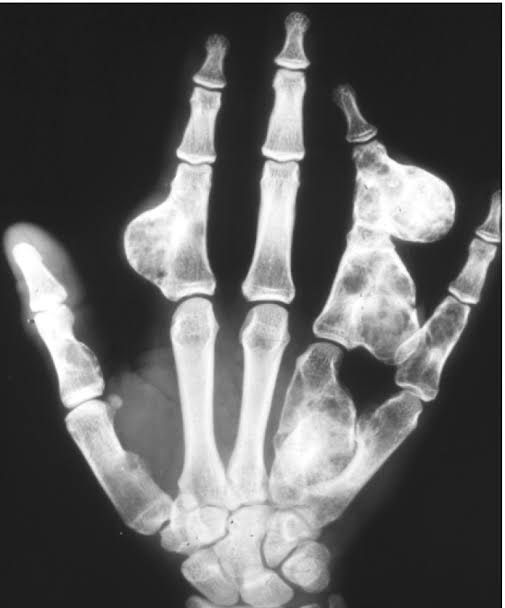

Chondroma is an intramedullary neoplasm made of well-differentiated hyaline cartilage.It is not cancer. The tumor usually occurs in the hands or feet, but it may also occur in the upper arm, thigh, collarbone, ribs, pelvis, spine, skull, and nasal sinuses. By: https://link.springer.com/chapter/10.1007/978-3-030-29676-6_15